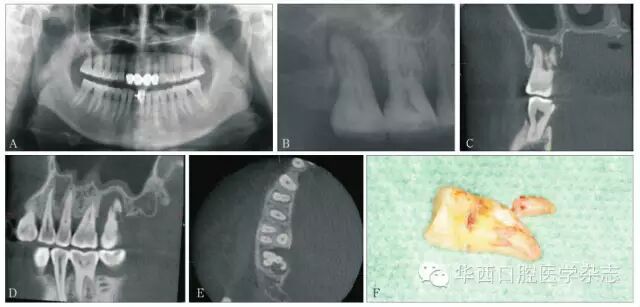

病例1:女性,56岁。主诉:右上后牙咀嚼不适3月。检查:17牙体完整,牙周黏膜正常,未探及牙周袋,叩(+),松Ⅰ°。全口卫生状况一般,牙结石Ⅰ°,色素Ⅰ°,可探及龈下牙结石。曲面体层片及根尖片见17根尖周骨质吸收,17远中牙槽嵴见致密条状影,CBCT冠状位、矢状位、轴位显示17腭根折裂,折片向远中移位。诊断:17腭根折裂。治疗:局部麻醉下拔除17,腭根折裂的断端及折片移位的方向与CBCT影像完全一致(图7)。

A:曲面体层片示17根周骨质吸收;B:根尖片示17远中牙槽嵴见致密条状影;CDECBCT冠状位、矢状位、轴位图像示17腭根折裂,折片向远中移位;F17拔除后见17腭根折裂。

7 病例1